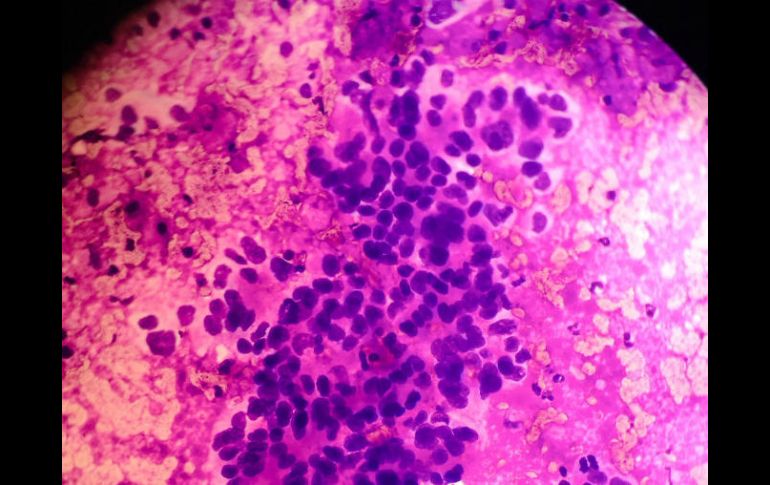

La sobrevida de pacientes con adenocarcinoma de páncreas es corta, el tiempo de vida es aproximadamente de seis meses. TWITTER / @Cell_ebrities